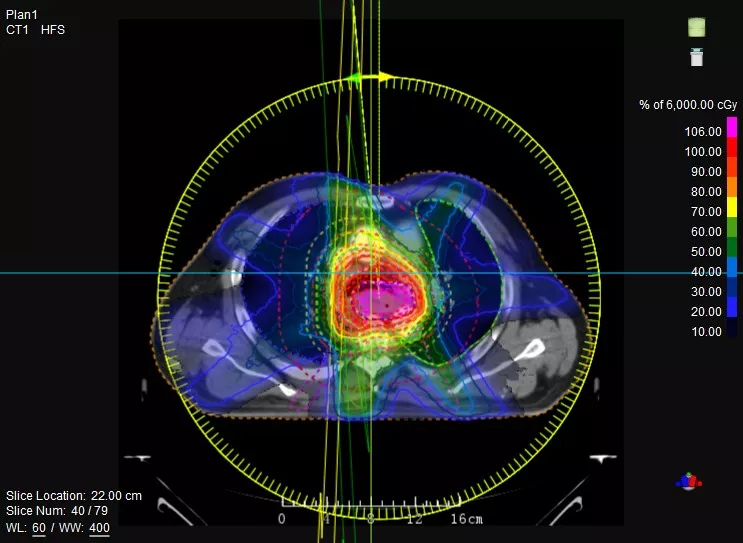

一款設(shè)備即可滿足CT模擬定位、CT影像引導(dǎo)、uARC動態(tài)旋轉(zhuǎn)調(diào)強(qiáng)放療等重要臨床應(yīng)用,無需科室/治療室間切換,一站完成放療全流程。

鼻咽癌患者,進(jìn)行旋轉(zhuǎn)容積調(diào)強(qiáng)治療(uARC)